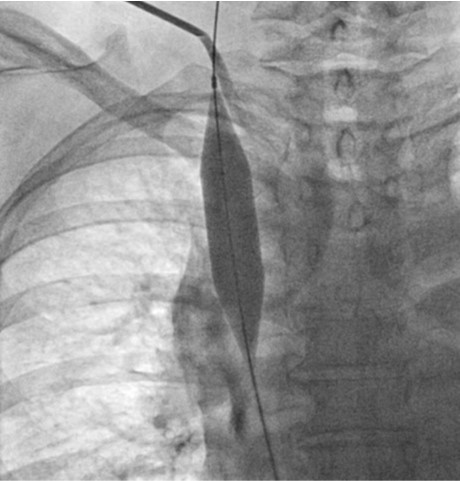

Fig. 7.

Fig 7. Fluoroscopic image showsdilatationof the occluded segmentby 16mmx4cm high pressure balloon.

초음파 유도 하에 우측 팔의 동정맥루 graft를 천자한 후 정맥조영술을 시행하여 우측 상완두정맥의 폐색을 확인함(Fig. 1). 5Fr Cobra 카테터(Cook, Bloomington, IN, USA)와 친수성 0.035 inch 유도철사(Terumo, Tokyo, Japan)로 폐색부위의 통과를 시도하였으나 실패함. 우측 대퇴정맥을 천자하고9Fr 65cm sheath (Arrow, Deutschland, Erding, Germany)를 상대정맥까지 진입시킨 후 5Fr Davis 카테터를 통해 약 2cm 길이의 상완두정맥 폐색 부위를 확인함(Fig. 2). Davis 카테터와유도철사로 상대정맥에서 우측 상완두정맥으로 통과를 시도함. 유도철사의 soft tip 부분으로 시도하였을 때 통과가 되지 않아서 반대쪽 hard tip 부분으로도 통과를 시도 하였으나 실패함(Fig.3). 유도 철사의 soft tip 과 hard tip 양쪽 모두 사용 하여 통과를 시도하였으나 막힌 부위의 위쪽 부분은 앞쪽(anterior side of the body) 을 향하고 있고 아래쪽 부분은 뒤쪽(posterior side of the body)를 향하고 있어서 천자 방향을 맞추기 어려웠음(Fig. 3). 우측 내경정맥을 천자하고 5Fr sheath를 삽입함. Sheath를 통해서 5FrKumpe 카테터와 0.035 inch 유도철사로 위에서 아래 방향으로 폐색부위 통과를 시도함. Hard tip으로 시술 도중 폐색혈관 주위로 유도 철사가 천자되어서 조영제의 누출이 있었으나 천자부위 주에 국한되어 있었고 임상적으로 문제 있는 혈류역학적 변화는 오지 않았음. Kumpe 카테터와 유도철사로는 천자 방향을 맞추기가 어려워서TIPS set (Cook, Bjaeverskov, Denmark)를 사용하기로 함. 천자된내 경정맥에 10Fr introducer sheath를 삽입하고 20G Colapinto needle을 폐색부위까지 진입시킴. 양쪽에서 정맥 조영술을 시행하여 폐색된 부위의 위치와 길이를 여러 각도에서 정확히 파악한 후, 폐색 부위를 천자함(Fig. 4). 천자 후 Colapinto needle을 통해 유도철사를 상대정맥에 진입시킴. 대퇴동맥을 통하여 삽입된 snare 카테터(ev3, Plymouth, MA, USA)를 이용하여 대퇴정맥 밖으로 유도철사를 빼냄(through and through technique)(Fig 5). 유도 철사만 통과된 상태에서 천자부 주위에 여러번의 천자로 인한 조영제 누출이 있었으나 주출된 조영제의 양이 적었으며 천자부 주위에 국한되어 있었음. Tractogram시행시 조영제의 누출은 보이지 않아서 유도 철사 주위에 국한 되어 있어서 풍선확장술을 시행 하기로 함(Fig. 6).대퇴 정맥을 통해 유도철사를 0.035 inch Amplatz wire(Cook, Bjaeverskov, Denmark)로 교체하여 내경정맥까지 진입시킨 후 풍선카테터 (Bard, NJ, US)를 삽입함.천자된 통로를 따라 직경 6 mm에서부터 16 mm까지의 풍선카테터로 차례대로 풍선확장술을 시행함(Fig. 7). 시술 후 정맥조영술에서 폐색부위는 개통되어 원활한 혈류를 보였음(Fig. 8). 시술 후에 오른쪽 팔의 종창은 호전됨.